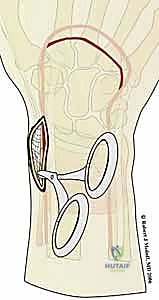

يقوم الدكتور هطيف بتقييم الكسر بناءً على نظرية الأعمدة (Column Theory)، والتي تقسم عظم الكعبرة البعيد إلى مكونات وظيفية محددة. كل شظية لها دور ميكانيكي، وفشلها يؤدي إلى نوع محدد من عدم الاستقرار:

- شظية العمود الكعبري (Radial Column Fragment):

هذا الجزء هو بمثابة الدعامة العظمية الجانبية على طول الحافة الكعبرية للرسغ (جهة الإبهام). تعتبر سلامته حاسمة للحفاظ على الطول الطبيعي لعظم الكعبرة ودعم عظام الرسغ (خاصة العظم الزورقي - Scaphoid) في موضعها الصحيح. يتصل بهذا العمود العضلة العضدية الكعبرية (Brachioradialis). عند كسر هذه الشظية، يمكن لهذه العضلة القوية أن تسحبها، مما يؤدي إلى تقصير العمود الكعبري وانضغاط عظام الرسغ في الشظايا المتبقية. يؤدي التفتت في هذه المنطقة إلى انهيار الهيكل الجانبي للرسغ.

- الحافة الأمامية (الراحية) للوجه الهلالي (Volar Lunate Facet):

هذا الهيكل التشريحي الصغير هو سطح رئيسي يتحمل الأحمال في الغضروف المفصلي، حيث ينقل القوة من اليد إلى الساعد. استقراره بالغ الأهمية لمنع انزلاق عظام الرسغ. عادة ما يواجه الجراحون نمطين خطيرين من عدم الاستقرار هنا:- نمط عدم الاستقرار الأمامي (Volar Instability): يتميز بتقصير وانزياح أمامي للحافة، مما قد يؤدي إلى خلع جزئي (Subluxation) لعظام الرسغ (خاصة العظم الهلالي - Lunate). هذا يضر بقدرة تحمل الوزن ويؤثر بشكل كبير على قوة القبضة.

- نمط عدم الاستقرار المحوري (Axial Instability): يؤدي الانضغاط المحوري القوي إلى دفع الحافة الأمامية نحو الانثناء الظهري. غالباً ما يؤدي هذا إلى خلع جزئي ظهري لعظام الرسغ، مما يعطل ميكانيكا المفصل بالكامل ويسبب ألماً مبرحاً.

- شظية الزاوية الزندية (Ulnar Corner Fragment):

عادة ما تشمل هذه الشظية النصف الظهري من الثلمة السينية (Sigmoid Notch)، وهي المنطقة التي يتمفصل فيها عظم الكعبرة مع عظم الزند. غالباً ما تكون هذه الشظية نتيجة انضغاط العظم الهلالي بقوة في السطح المفصلي. يمكن أن يؤدي أي انزياح متبقٍ لهذه الزاوية إلى عدم استقرار كبير في المفصل الكعبري الزندي البعيد (DRUJ). هذا المفصل هو المسؤول عن حركة دوران الساعد (الكب والاستلقاء - Pronation & Supination). إهمال تثبيت هذه الشظية يؤدي حتماً إلى تقييد دوران الساعد وألم مزمن عند تدوير مفتاح أو فتح مقبض الباب.

- الجدار الظهري (Dorsal Wall):

يحدث تفتت الجدار الظهري عادة مع إصابات الانثناء الظهري (الامتداد المفرط للرسغ) أو التحميل المحوري عالي الطاقة (مثل حوادث السيارات أو السقوط من ارتفاع). يساهم هذا المكون بشكل كبير في عدم استقرار الكسر الكلي. نظراً لأن الأوتار الباسطة للأصابع تمر مباشرة فوق هذا الجدار، فإن أي بروز عظمي هنا يمكن أن يؤدي إلى احتكاك وتمزق الأوتار لاحقاً.

- الشظايا المفصلية الحرة (Free Intra-articular Fragments):

في الكسور شديدة التفتت، قد تنفصل قطع صغيرة من الغضروف والعظم أسفله (Osteochondral fragments) وتنغرس داخل تجويف الكردوس (Metaphysis). يؤدي هذا إلى "فجوات" في السطح المفصلي وعدم تطابق (Step-off). يعد تحديد هذه الشظايا باستخدام الأشعة المقطعية، ثم استخراجها وإعادتها إلى مكانها بدقة (مثل تركيب قطع الفسيفساء) أمراً حيوياً لاستعادة سطح مفصل أملس يمنع خشونة المفاصل المبكرة.